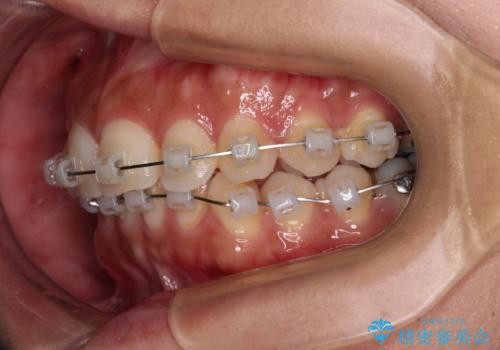

目立つ八重歯を改善 ワイヤー装置での抜歯矯正

- クリアブラケット

上顎小臼歯を抜歯するかどうか悩みましたが、八重歯の後方に失活歯があること、治療前に上顎正中が概ね人中に合っていることから、右上第二小臼歯を抜歯することとしました。

片側での抜歯であると、正中が抜歯した方向にずれていくため、左上の奥歯を遠心移動させる目的でアンカースクリューと補助装置を併用した上で、ワイヤー装置にて矯正治療を行うこととしました。

上顎の正中位置をほぼ保った状態で、綺麗に仕上げることができました。